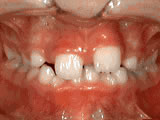

Phase One

This boy’s parents were concerned about both aesthetics and the health of the erupting permanent teeth when they brought him to the orthodontist at age eight. The lower front teeth were crowded and touching the palate, and the upper front teeth were extremely displaced from their normal positions. After 12 months of Phase-One treatment with an expander and partial braces, the patient’s appearance and dental function were vastly improved.